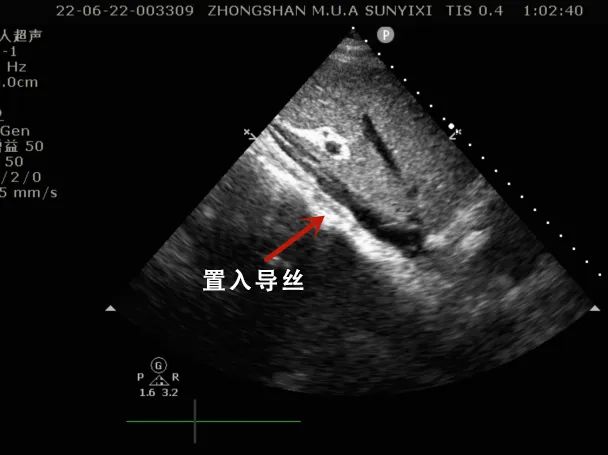

床旁超声引导下进行Crescent置管及定位:

在床边心超辅助下定位置管

同时,由于缺氧引起心律失常,该患者生命危在旦夕。郑教授当机立断,在取得家属同意后,立即指导心血管外科高级生命支持团队,在床边心脏彩超辅助下,采取单管双腔V-V ECMO辅助,尽快改善了患者氧合,保护了患者脏器及脑组织氧供给,尽最大可能降低了因缺氧所可能导致的不可逆并发症。

接郑俊猛教授指示后,在梁石副教授,陶俊区长带领下,高级生命支持团队迅速超声定位置管,15分钟为病毒性脑炎患者开放生命通路。